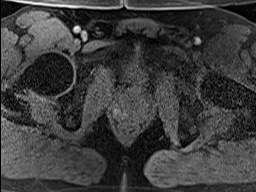

Tables 1 and 2 show our quantitative results: PSNR between the style (image we want to transfer style from) and generated image, SSIM and MS-SSIM between the content (image we want to take structure from) and generated image and finally, our proposed weighted SSIMs. For each style transfer direction and metric, our method consistently outperforms the other approaches. Figures 2 and 3 qualitatively highlight the good results of our method on 2D and 3D datasets. In addition, quantitative results on both figures show that our proposed metric preserves qualitative ordering of results for both style and content. In comparison, metrics such as SSIM struggle to accurately correlate to visual results.

Qualitative evaluation shows that the proposed method leads to sharper images, better content preservation, better localised CE and realistic MRI appearance. Quantitatively, we outperform the other algorithms with each metric, for each style transfer direction. While we expected that adding CE to images would be an easier task than removing CE, we found that for both tasks the method exhibits similarly performing quantitative and qualitative results. The results for style transfer with the kidney data show that when there is clear CE, it is easier to perform style transfer in both directions. However, when style transfer is performed on the prostate data, the model struggles in comparison to the kidney data. This may be due to the enhancement of the prostate being less defined than the kidney data. In figure 3(b), we can see the prostate with CE. Compared to figure 2(b) showing kidneys with CE, it is harder to determine the edges. The two original images shown in figures 3(a) and 3(b) are clear and easy to see some edges of prostate, in other images, it is harder to see the edges of the prostate.

(C) CW-SSIM: 0.68

(S) CW-SSIM: 0.61

(C) CW-SSIM: 0.54

(S) CW-SSIM: 0.51

(C) CW-SSIM: 0.42

(S) CW-SSIM: 0.67

(C) CW-SSIM: 0.93

(S) CW-SSIM: 0.73